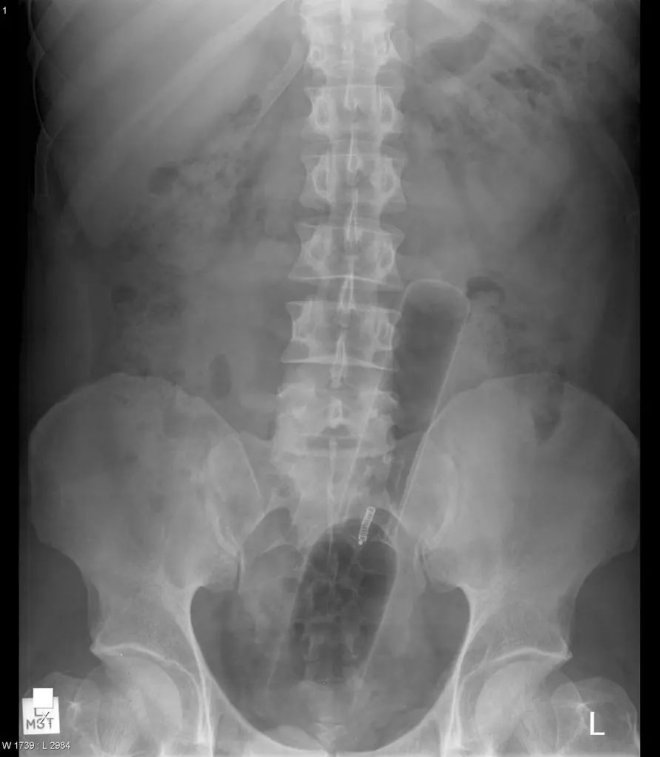

小胡瓜

19厘米長,頂端已經到了膽囊附近,這種病例非常罕見,使得醫生很納悶是怎麼把蔬菜塞進直腸的